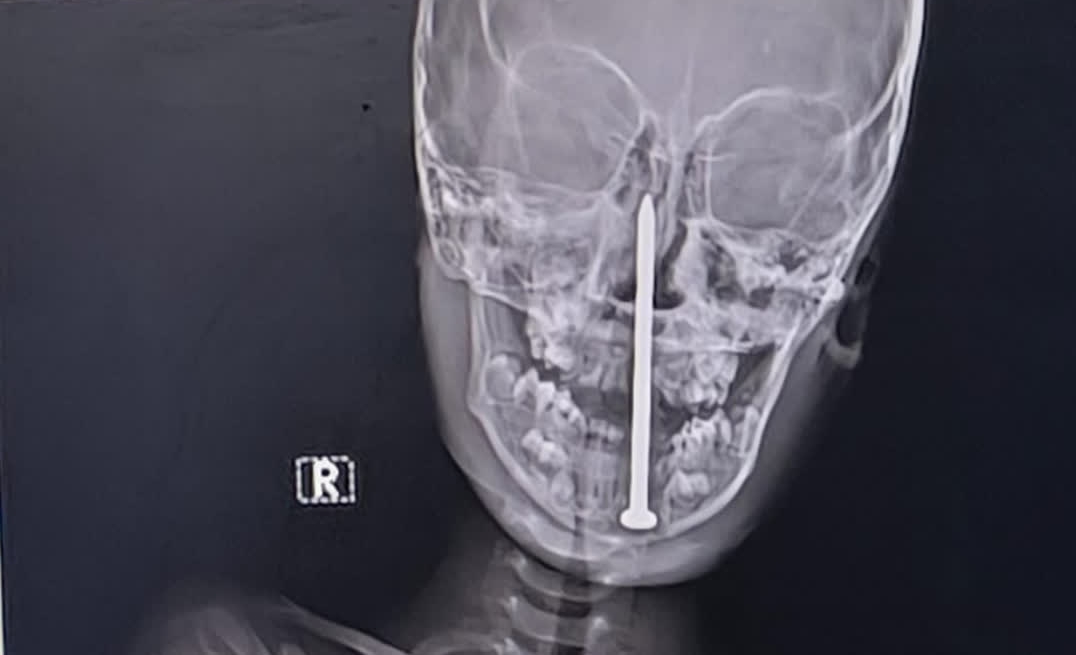

V Indiji se je zgodila grozljiva nesreča. Sedemletni deček je med igro padel na osem centimetrov dolg žebelj, ki mu je prebodel glavo. Sledila je zahtevna deseturna operacija.

Sedemletni deček iz okrožja Balrampur v indijski zvezni državi Uttar Pradesh je med igro padel na osem centimetrov dolg žebelj, ki se mu je zaril v glavo, poročajo indijski mediji.

Družina ga je nemudoma odpeljala v lokalno bolnišnico, vendar se je njegovo stanje kmalu poslabšalo, zato so ga premestili v večji travmatološki center v mestu Lucknow. Tamkajšnji zdravniki so opravili MRI- in CT-preiskave, ki so pokazale, da je osem centimetrov dolg žebelj nevarno prebil večjo žilo v njegovih možganih.

Z mikrokirurškimi tehnikami in sodobno nevronavigacijo so žebelj uspešno odstranili, ne da bi pri tem poškodovali možgane. Deček tako ni več v smrtni nevarnosti in že okreva, še poroča India Today.